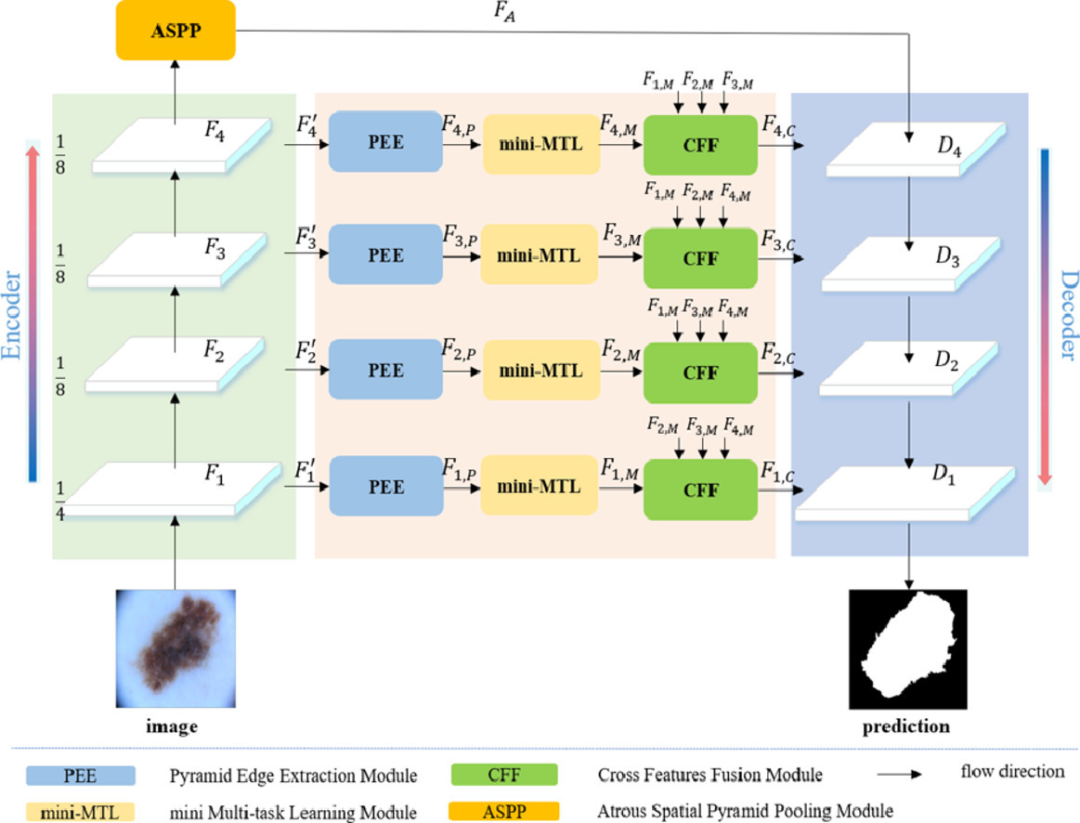

BA-Net

Paper: 《Boundary-aware context neural network for medical image segmentation》

Accepted by MIA 2022.

BA-Net 是一个针对 2D 医学图像分割并基于编解码结构所设计的边界感知上下文神经网络,可以捕获更丰富的上下文并保留精细的空间信息;其次,通过在编码器子网络的每个阶段,应用金字塔边缘提取模块来获得多粒度边缘信息;最后,一个新设计的迷你多任务学习模块用于联合学习分割对象掩码和检测病变边界,其中引入了一个新的交互式注意层来桥接这两个任务。通过这种方式,实现了不同任务之间的信息互补,有效地利用边界信息为更好的分割预测提供了强有力的线索。最后,交叉特征融合模块用于选择性地聚合来自整个编码器子网络的多级特征。通过级联这三个模块,每个阶段的更丰富的上下文和细粒度特征被编码,然后传递给解码器。